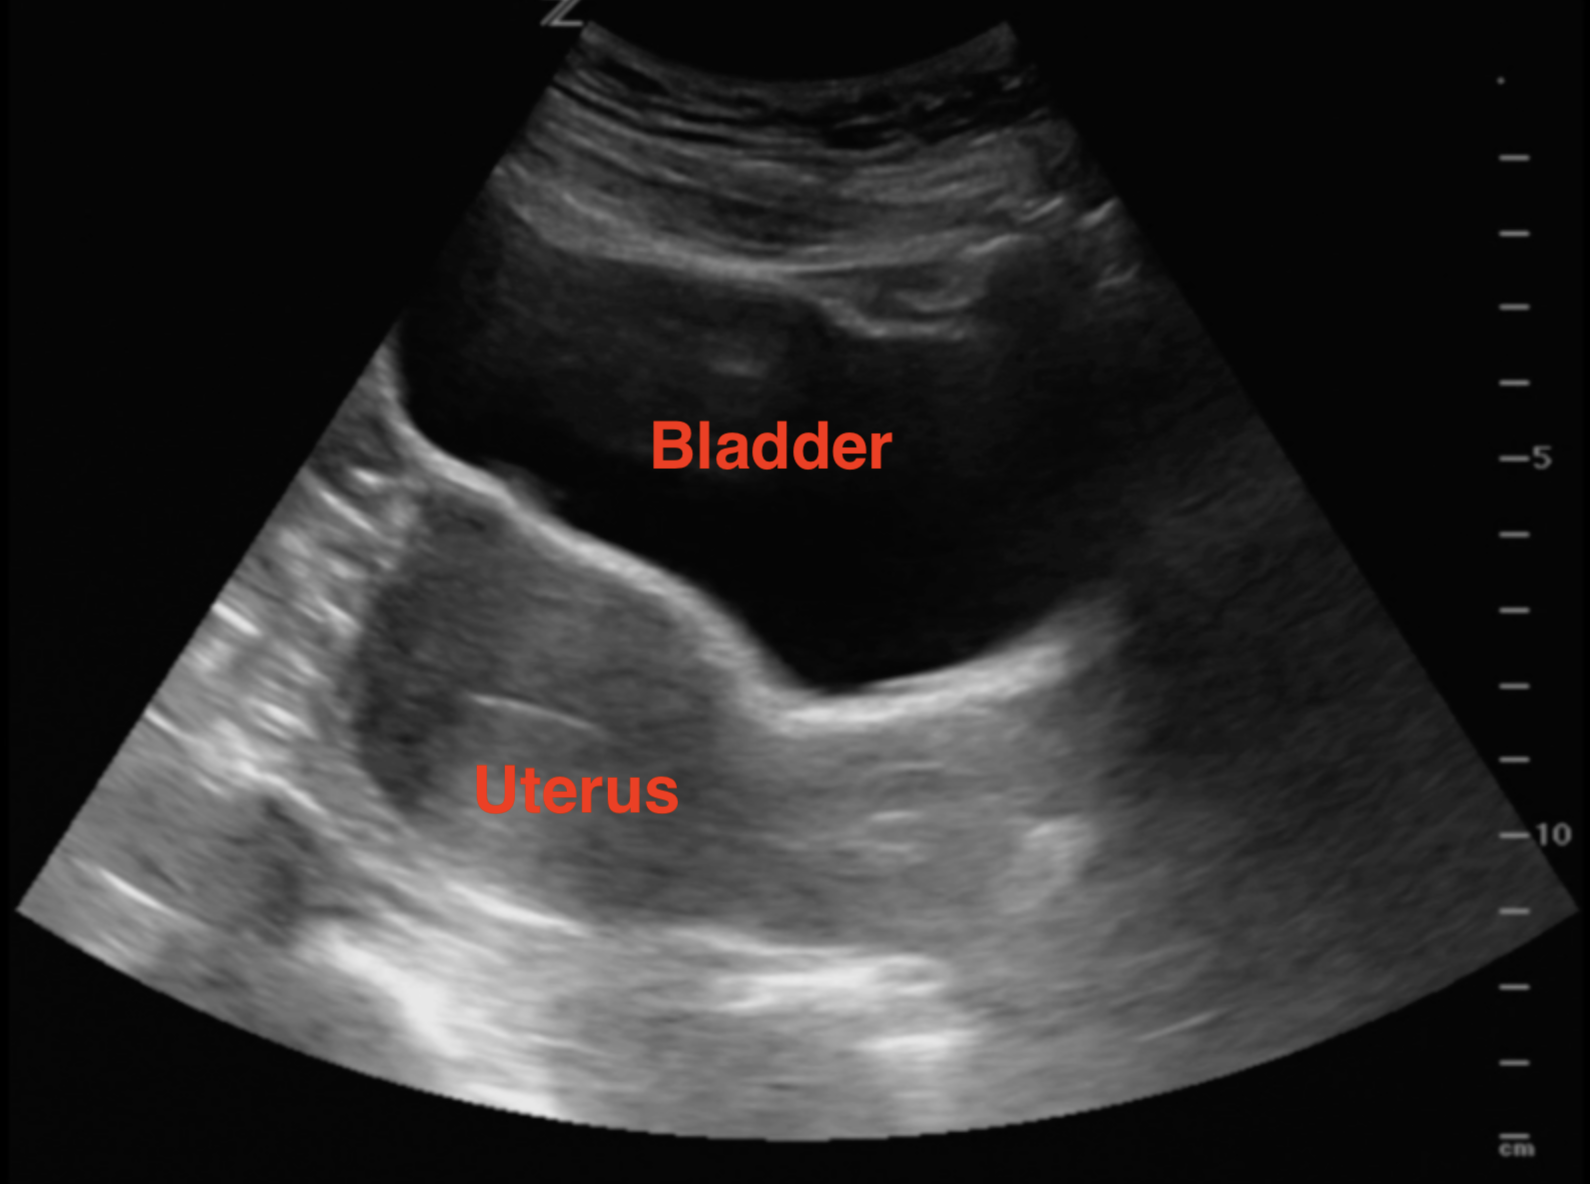

415 Cleft Lip and Palate. Its possible to have a positive pregnancy test even if you arent technically pregnant. A fetal ultrasound or sonogram is an imaging technique that uses high-frequency sound waves to produce images of a baby in the uterus.

When You Can See A Baby On The Ultrasound Scan